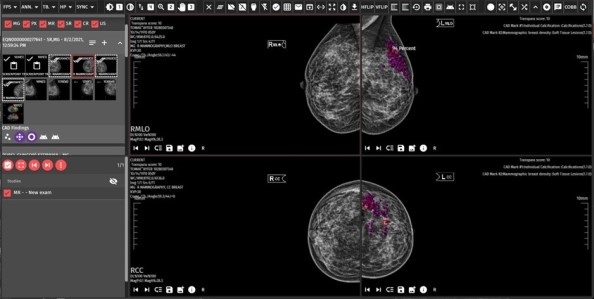

MoreAdvanced Image Processing Tools

Image Processing Tools That Can Work with Different Segmentations